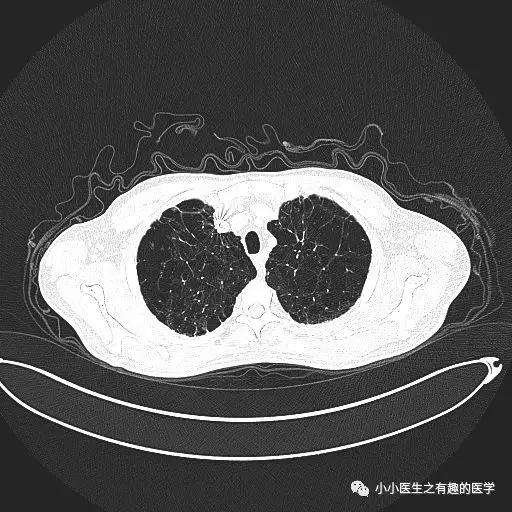

经典的间质性肺炎,就是一张网!

1.胸膜下2.网格状很多间质性肺炎,都有这个特征,是间质性肺炎的入门知识,也是很重要的知识。

乌漆嘛黑的是肺气肿。

间质性肺炎 合并 肺气肿